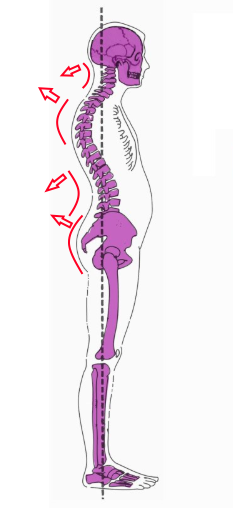

Когда у нас слабый пресс и сильная спина, то вертикально, и относительно “ровно” можно держать себя и так.

Обратите внимание, что работа вся направлена назад и происходит в спине и шее. Вперед нет необходимости что-то наклонять – у нас спереди руки, плечи, живот. Голова сама падает вперед. Весь вес – направлен вперед и без участия мышц. Красные стрелки напоминают именно те места, где чаще всего и болит, не так ли?

Но если взять не ситуацию с лордозом, а нормальную осанку – когда плечи ровно, позвоночник ровный, то становится видно, что передним мышцам нужно работать больше, а вот задним – меньше!

С шеей ровно та же история – вся наша жизнь – наклоны головы вперед.